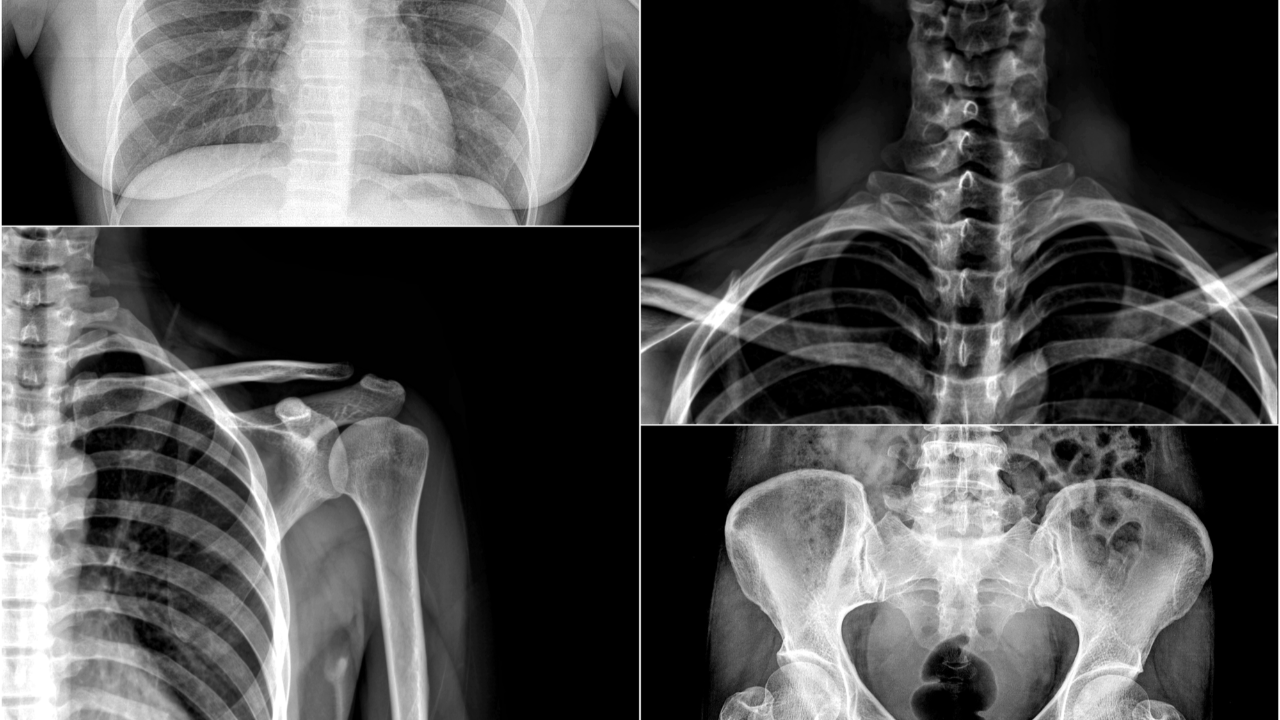

Congenital Anomalies & Skeletal Variants DXI on NBCE Part III: How to Avoid the Most Common Board Traps

Congenital anomalies and skeletal variants are one of the highest missed categories in the Diagnostic Imaging Interpretation (DXI) portion of NBCE Part III.

Congenital anomalies and skeletal variants account for approximately 15% of DXI content on NBCE Part III.

High-Yield Congenital & Variant Topics on DXI

NBCE repeatedly tests a predictable set of conditions. If you know how these appear on imaging—and what they mean clinically—you’re ahead of most students.